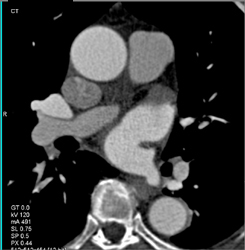

CASE NUMBER 667

Focal Dilatation of the RCA With Remodeling